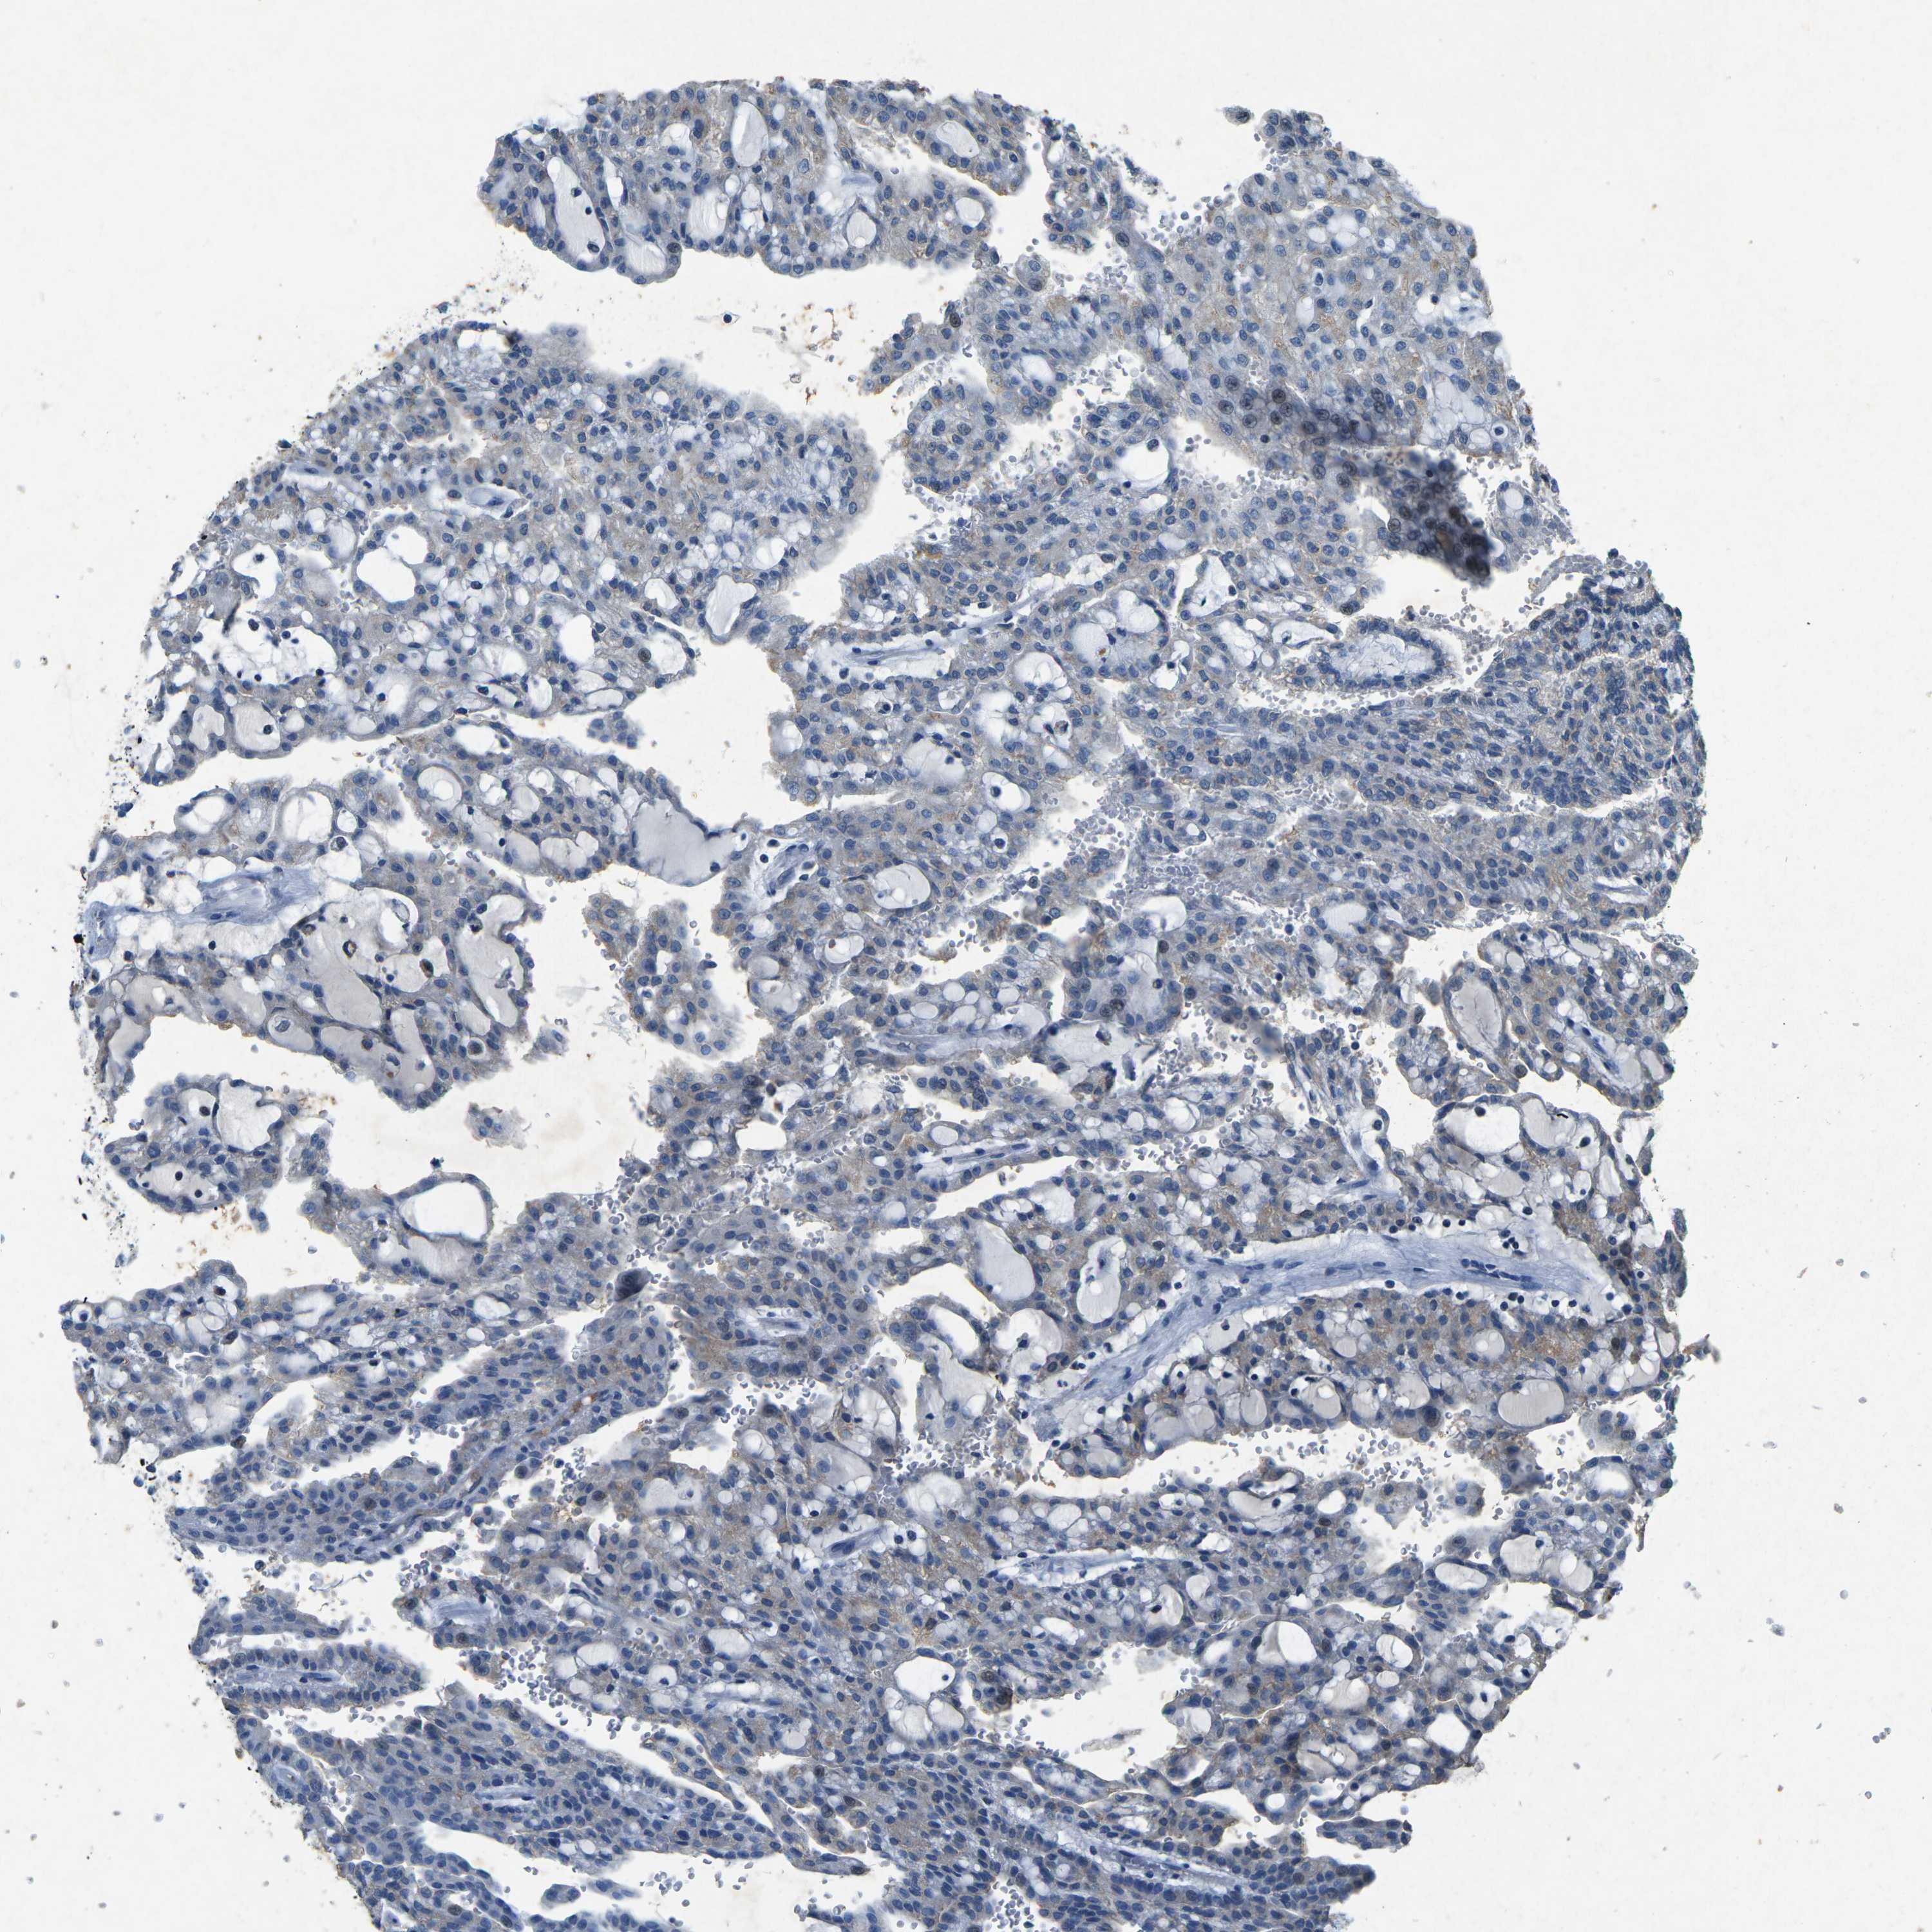

KIDNEY RENAL CLEAR CELL CARCINOMA (VALIDATION) - Interactive survival scatter ploti

The Survival Scatter plot shows the clinical status (i.e. dead or alive) for all individuals in the patient cohort, based on the same data that underlies the corresponding Kaplan-Meier plots. Patients that are alive at last time for follow-up are shown in blue and patients who have died during the study are shown in red.

The x-axis shows the expression levels (FPKM) of the investigated gene in the tumor tissue at the time of diagnosis. The y-axis shows the follow-up time after diagnosis (years). Both axes are complimented with kernel density curves demonstrating the data density over the axes. The top density plot shows the expression levels (FPKM) distribution among dead (red) and alive patients (blue). The right density plot shows the data density of the survived years of dead patients with high and low expression levels respectively, stratified using the cutoff indicated by the vertical dashed line through the Survival Scatter plot. This cutoff is automatically defined based on the FPKM cutoff that minimizes the p-score. The cutoff can be changed by dragging the vertical line or by entering a cutoff value in the square labeled "Current cut-off".

Under the Survival Scatter plot the p-score landscape (black curve; left axis) is shown together with dead median separation (red curve; right axis). Dead median separation is the difference in median mRNA expression between patients who have died with high and low expression, respectively. It is calculated as follows: median FPKM expression of dead patients with high expression - median FPKM expression of dead patients with low expression. This is intended to aid the user in visually exploring custom cutoffs and the associated p-scores and dead median separation.

Individual patient data is displayed and can be filtered by clicking on one or more of the category buttons on the top of the page. Categories describing expression level and patient information include: high, low, alive, dead, female, male and tumor stages. The scale of the x-axis can be toggled between linear and log-scale by clicking on the "x log" button. Mouse-over function shows TCGA ID, patient information and mRNA expression (FPKM) for each patient.

& Survival analysisi

Kaplan-Meier plots summarize results from analysis of correlation between mRNA expression level and patient survival. Patients were divided based on level of expression into one of the two groups "low" (under cut off) or "high" (over cut off). X-axis shows time for survival (years) and y-axis shows the probability of survival, where 1.0 corresponds to 100 percent.

PLG is not prognostic in Kidney Renal Clear Cell Carcinoma (validation)

: 0.86

TCGA RNA samplesi

RNA-seq data is reported as average FPKM (number Fragments Per Kilobase of exon per Million reads), generated by the The Cancer Genome Atlas (TCGA) .

Normal distribution across the dataset is visualized with box plots, shown as median and 25th and 75th percentiles. Points are displayed as outliers if they are above or below 1.5 times the interquartile range. FPKM values of the individual samples are presented next to the box plot.

Average pTPM 15.6

Number of samples 100